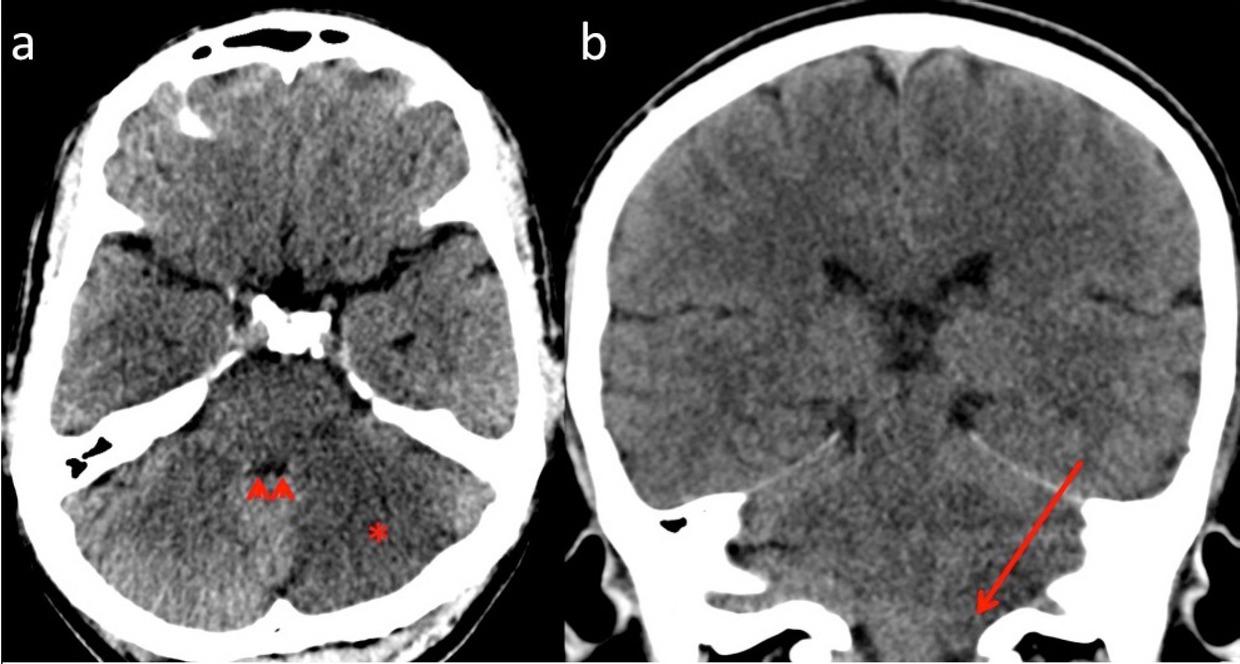

Fig. 1